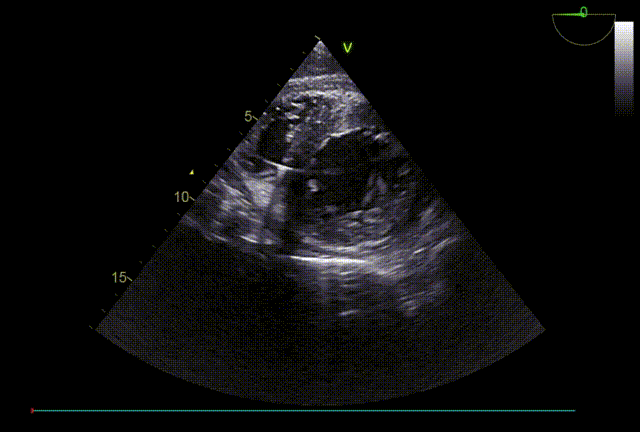

TTE入院

TTE